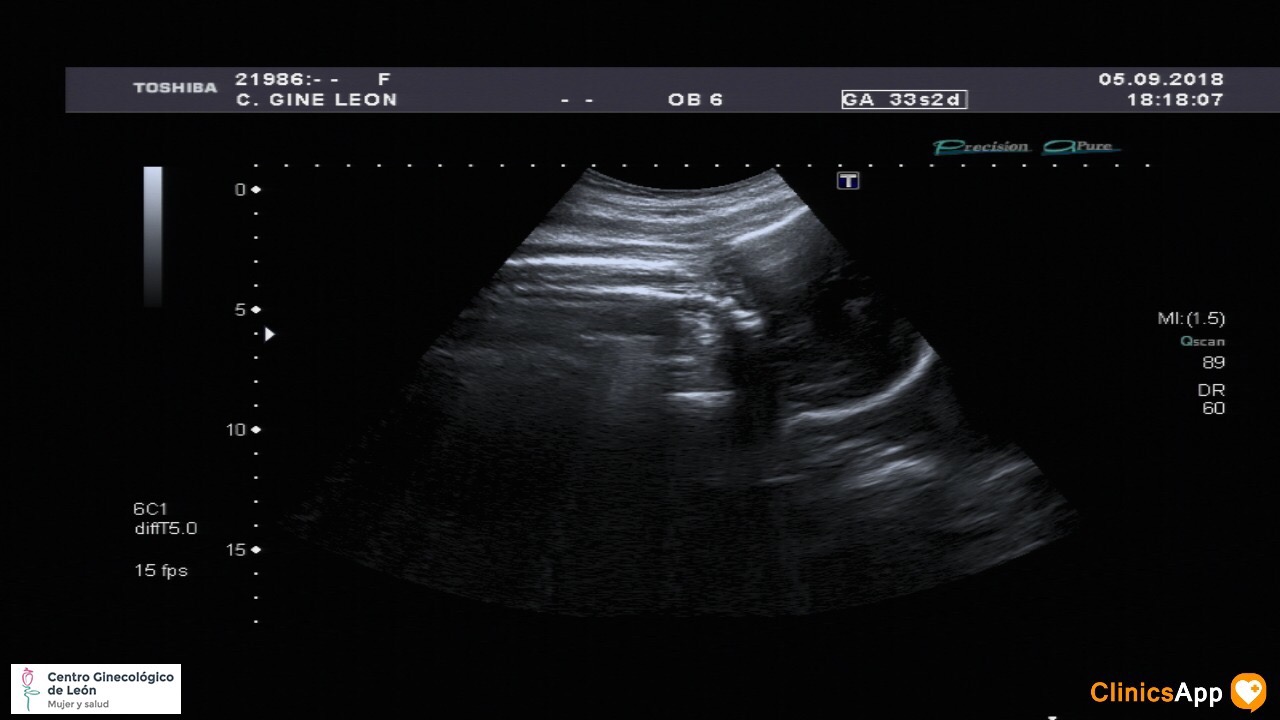

Nueva ecografía de la hermana de Mateo Nueva ecografía… y aún sin nombre. Ya pesa más de 2Kg, así que empieza a estar más apretada. Fecha publicación 05/09/2018 Publicada por papá Publicada en Fotos, Galerías, Prenatal Comentarios 0 Entrada anterior: Con mamá al parque Entrada siguiente: Caco balí n° 23 Deja una respuesta Cancelar la respuestaComentario * Nombre * Correo electrónico * Web Guarda mi nombre, correo electrónico y web en este navegador para la próxima vez que comente. Recibir un correo electrónico con los siguientes comentarios a esta entrada. Δ